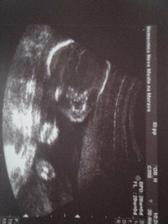

30.11. - velký UZ ve 20 tt - vše dopadlo výborně, srdíčko je v pořádku a na 90 % mi pod srdcem roste HOLČIČKA !!